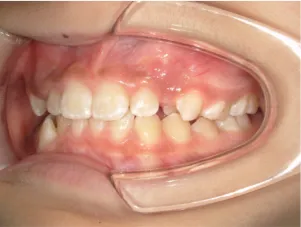

*マルチブラケット法移行前

治療中④中1:治療中 マルチブラケット法へ移行

| 行ったご提案・診断内容 | 生え変わりが終わってなくマルチブラケット法による咬合治療には早い時期のため、顔立ちの成長を促す目的で歯列弓(アーチ)の拡大と前歯を並べながら永久歯が生えるのを待ち、咬合治療開始時に再診断で抜歯、非抜歯を最終検討する提案をしました。 再診断時(写真②)、歯列の拡大と上顎前歯の並べ替えはされていましたが八重歯となったため抜歯、非抜歯を検討しました。 口元は特に問題がなく非抜歯で八重歯を改善するためのスペースを作ることが可能なため非抜歯治療を提案しました。 治療は、 ・拡大および上顎左右6を遠心移動させてスペースを作る 予定装置 |